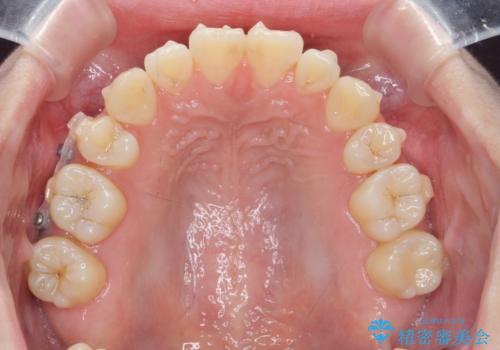

- 前歯の角度 奥歯の噛み合わせの改善をするために、矯正治療を希望され来院されました。

右側奥歯は上顎が相対的に前方に位置し(上顎前突)、そのため前歯の角度も突き出たようになり出っ歯のように見える状態でした。

マイクロインプラントを用いて、上顎奥歯を後方に移動させることで噛み合わせ・前歯の角度を改善していきます。

少し時間はかかりましたが、しっかりと綺麗な歯並びに仕上げることができ、大変喜んでいただくことができました。